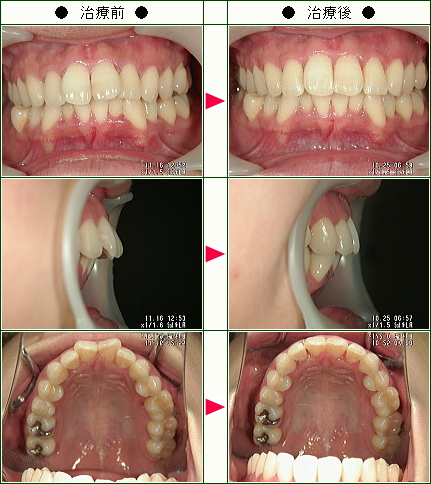

☆歯のデコボコ矯正症例(まほ様 21歳 女性)